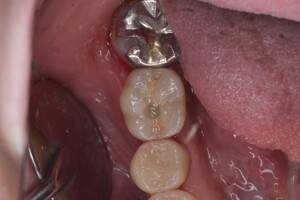

インプラント治療の症例4

口腔内写真

- Befor

- After

| 治療方針 | 元々支台歯に負荷がかかりやすいとされている延長ブリッジを抜歯し、1本単体でしっかりかめるようにインプラントを2本埋入した。骨吸収も進んでいたため、※GBR法で骨造成を同時に行った。 治療と並行して、全顎的な歯周病治療も行い、今後は歯周病が進行しないよう、こまめにメンテナンスに通っていただく。 |

| 担当者所見 | 6番は歯根分割された被せ物が7番の欠損部との延長ブリッジとされており、強い咬合と歯周病も相まって負荷がかかり動揺し、歯として機能しなくなったため、抜歯となった。 |